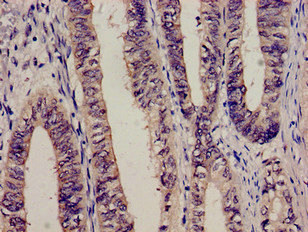

Immunohistochemistry analysis of human colon cancer using CSB-PA10599A0Rb at dilution of 1:100